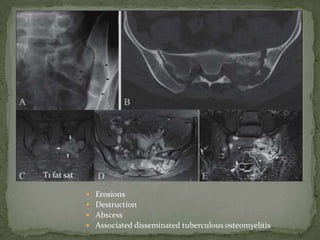

 Erosions

 Destruction

 Abscess

 Associated disseminated tuberculous osteomyelitis

T1 fat sat